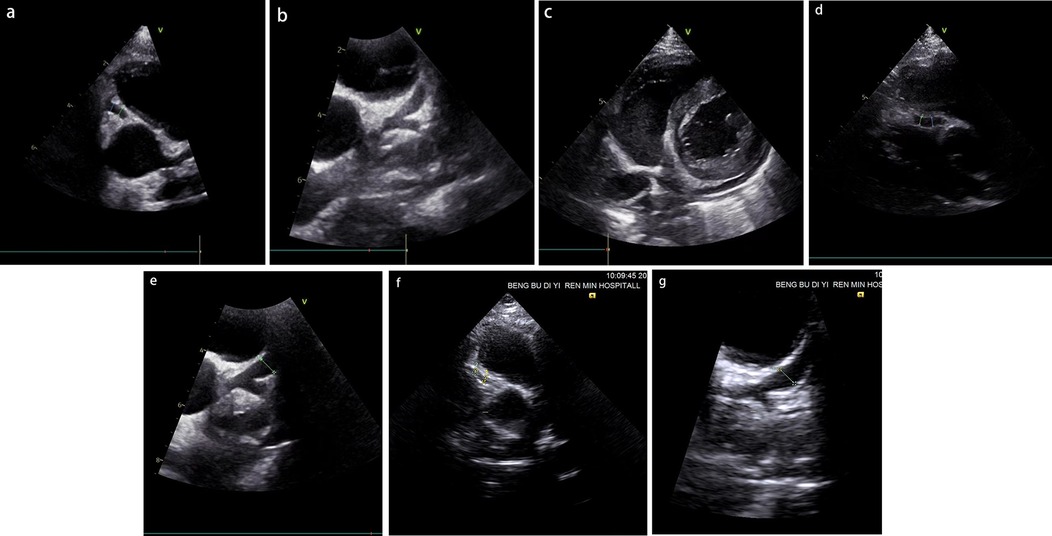

Physical examination upon admission: Temperature 38.4°C, no obvious conjunctival congestion, no dryness or redness of the lips, no “strawberry tongue,” no changes in extremities, several enlarged lymph nodes palpable in the neck. Scattered red rashes were observed over the whole body, raised above the skin surface, non-blanching on pressure, partially confluent, and without significant pruritus. Dry and moist rales were heard in both lungs. Abdomen slightly distended, with tenderness in the upper abdomen but no rebound tenderness. The liver is approximately 2 cm below the costal margin, and the spleen is approximately 1.5 cm below the costal margin. Blood pressure is significantly reduced (71/45 mmHg). Laboratory examinations: WBC count normal (4.79 × 109/L), CRP elevated (158.14 mg/L), erythrocyte sedimentation rate (ESR) slightly elevated (21 mm/h), PLT count reduced (44.00 × 109/L), Hb reduced (104 g/ L), SAA elevated (321.48 mg/L), IL-6 elevated (143 pg/mL), D-dimer elevated (7.23 µg/mL), albumin reduced (26.00 g/ L), transaminases elevated (ALT 136 U/L, AST 120 U/L), and pro-brain natriuretic peptide (pro-BNP) elevated (6,968 pg/mL). Chest computed tomography (CT) suggested pneumonia with pleural effusion (Figure 1), and chest ultrasound showed left-sided pleural effusion of 51 mm. Abdominal CT revealed peritoneal effusion with cholecystitis, and ultrasound showed a thickened gallbladder wall and splenomegaly. Based on the child's clinical symptoms and auxiliary examination results, the preliminary diagnosis was severe pneumonia complicated by septic shock. Methylprednisolone was administered for anti-inflammatory treatment, meropenem for infection, low molecular weight heparin for anticoagulation, fluid resuscitation, dopamine and dobutamine for blood pressure support [although foreign literature had already reported that adrenaline and noradrenaline were the firstline inotropic agents for septic shock, the guidelines in China were not updated until 2025 (5)], albumin administration for hypoalbuminemia, and intravenous immunoglobulin (IVIG, 1 g/kg/day for 2 days) for immunomodulation. After 5 days of treatment (on day 12 of illness), the child still presented with recurring fever and abdominal pain, but the rash had gradually subsided. Physical examination revealed slight conjunctival congestion, slightly red lips, and a strawberry tongue. Several enlarged lymph nodes were palpable in the neck. Blood tests indicated elevated serum ferritin levels (2,086 ng/mL) with nagetive blood culture report, so KD was highly suspected, and further tests were conducted. Neck ultrasound showed enlarged cervical lymph nodes (2 cm × 2 cm), and cardiac echocardiogram revealed left main coronary artery (LMCA) dilation (4.0 mm, Z score + 2.93), left circumflex artery dilation (LCX 3.2 mm, Z score + 3.15), left anterior descending artery dilation (LAD 4.4 mm, Z score + 5.73), and right coronary artery widening (RCA 3.5 mm, Z score + 2.36), with mild pericardial effusion (Figure 2). Hemophagocytic cells were shown on the bone marrow biopsy (Figure 3). Considering the progressive increase in ferritin levels, a sharp decrease in platelets, elevated AST, and reduced fibrinogen (from 3.52 to 1.39 g/L) during the course of illness, the child was diagnosed with KDSS, MAS, severe pneumonia, and cholecystitis. On the 12th day of illness, IVIG (2 g/kg) was administered along with a methylprednisolone pulse therapy (30 mg/kg/day for 3 days) and oral aspirin 100 mg daily for antiplatelet therapy due to his poor liver function. After finishing IVIG infusion (on day 13 of illness), the child's temperature normalized, follow-up chest CT indicated improvement of pneumonia, and corticosteroids were tapered. However, on day 20, fever recurred when methylprednisolone was tapered to 1 mg/kg/day, accompanied by mild erythema on both palms. CRP reelevated to 38.43 mg/L, suggesting an IVIG non-responding KD. Echocardiography showed a progressive CAA (Table 1). So infliximab (5 mg/kg) combined with methylprednisolone (2 mg/kg/day) was given. His fever and symptoms resolved completely, and the corticosteroid was tapered within 3 weeks. Prior to discharge (on day 33 of illness), an echocardiogram showed multiple CAAs (LMCA 3.7 mm, Z score + 2.24; LCX 4.3 mm, Z score + 4.9; left ascending artery (LAD) 6.3 mm, Z score + 10.49; RCA 4.3 mm, Z score + 4.14) (Figure 2). PLT count increased to 408 × 109/L, and then oral rivaroxaban 7.5 mg and aspirin 100 mg daily were prescribed for antithrombosis (6), and coronary artery computed tomography angiography (CTA) was performed (Figure 4). The child was discharged after 30 days of hospitalization and was scheduled for regular outpatient follow-up. The CTA 3 months after discharge showed significant improvement in all three branches, with the maximum diameter 6.8 mm in LAD (Figure 4); therefore, rivaroxaban was replaced with clopidogrel. At the last follow-up (6 months after the onset of illness), the echocardiogram showed significant regression of the coronary aneurysms (LMCA 3.2 mm, Z score +1.08; LCX 2.6 mm, Z score + 1.17; LAD 5.0 mm, Z score + 7.24; RCA 2.7 mm, Z score + 0.58), and only aspirin was continued.

Figure 2. (a–c) The results of the patient's initial coronary artery echocardiography following hospital admission (on day 12 of illness). (d,e) The findings obtained prior to discharge (on day 33 of illness). (f,g) The results from the most recent follow-up evaluation (6 months after the onset of illness). RCA dilation with a diameter of 3.5 mm (a), left coronary artery dilation with LMCA 4.0 mm, left ascending artery (LAD) 4.4 mm, LCX 3.2 mm (b), and mild pericardial effusion (c) were shown. RCA dilation with a diameter of 4.3 mm (d), left coronary artery dilation with LMCA 3.7 mm, LAD 6.3 mm, LCX 4.3 mm (e), RCA dilation with a diameter of 2.7 mm (f), left coronary artery dilation with LMCA 3.2 mm, LAD 5.0 mm, LCX 2.6 mm (g).